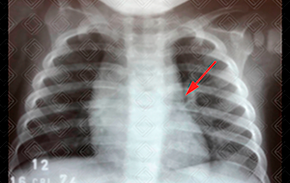

Texto alternativo para a imagem Figura 1. Créditos: Dra. Elazir Mota - Rio de Janeiro/RJ

• Sinal do barco a vela: Embora clássico, é um achado pouco frequente nas radiografias de tórax, sendo observado em somente 5% dos casos. Na figura 1 , observa-se o lobo tímico direito com aspecto triangular, com uma base nitidamente demarcada pela fissura menor;